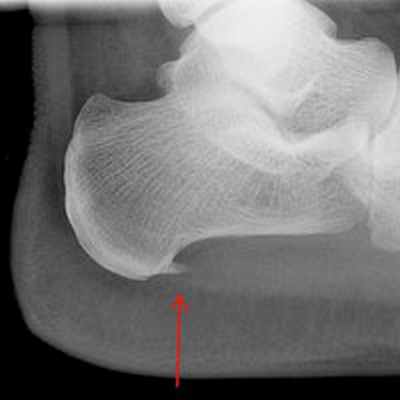

Уточнить диагноз позволяет рентгенография стопы. При этом на рентгенограмме виден костный нарост.

После консультации диагноз «пяточная шпора» подтвердился – на рентгеновском снимке костный нарост был четко виден. На приеме специалисты клиники объяснили женщине: методы, на которые она возлагала надежды, эффективны только в самом начале заболевания. А так как Наталье Борисовне пяточная шпора не один год мешает нормально жить, операция была единственным верным решением. Более того, медлить с вмешательством было ни в коем случае нельзя.

Ренген-снимок до операции Рентген стопы после операции

Диагностикой и лечением пяточной шпоры занимается врач ортопед. Основным способом выявить патологию и оценить степень ее развития является рентгенография. На снимке хорошо виден костный нарост, его форма, расположение и величина.

Пяточная шпора представляет собой депозит кальция на нижней части пяточной кости. На рентгеновском снимке, пяточная шпора может выступать вперед на 0.5-1 см. Хотя пяточные шпоры часто безболезненны, тем не менее, они могут быть причиной достаточно сильных болей. Пяточные шпоры часто ассоциированы с подошвенным фасцитом. Подошвенный фасцит является наиболее частой причиной болей в нижней части пятки. Приблизительно 2 миллиона пациентов в США лечатся по поводу подошвенного фасцита каждый год. Подошвенный фасцит возникает, когда сильная полоска ткани, которая поддерживает свод стопы (плантарная фасция), раздражается и воспаляется. Пяточные шпоры на задней части пятки нередко также ассоциированы с воспалением ахиллова сухожилия (тендинитом) и могут быть причиной болезненности и болей в задней части пятки, усиливающейся при разгибании стопы.

После изучения истории болезни, жалоб пациента, врач проводит осмотр ноги: наличие высокого свода, площадь болезненности в области пятки, наличие ограничений подвижности в стопе. Для верификации диагноза могут потребоваться инструментальные методы исследования. Рентгенография позволяет получить четкое изображение костных тканей. Это метод исследования дает возможность исключить другие причины болей в пятке,такие как перелом или артроз. Пяточная шпора хорошо визуализируется при рентгенографии.